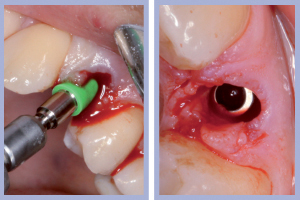

- Figg. 11a, b – Inserimento dell’impianto di destra. Max Stability da 3,75 x 12 mm

- Figg. 12a, b – Impianto di destra inserito

- Figg. 13a, b – Inserimento dell’impianto di sinistra. Max Stability da 3,75 x 12 mm

- Figg. 14a, b – Impianto di sinistra inserito

Il posizionamento di due impianti Max Stability da 3,75 mm di diametro e 12 mm di lunghezza ha consentito l’ottenimento di una elevata stabilità primaria, essenziale per portare a termine il carico immediato programmato. Nel caso dell’impianto Max Stability, la forma tronco-conica è associata alla presenza di spire molto prominenti che garantiscono un’elevata stabilizzazione anche in osso di qualità scadente.